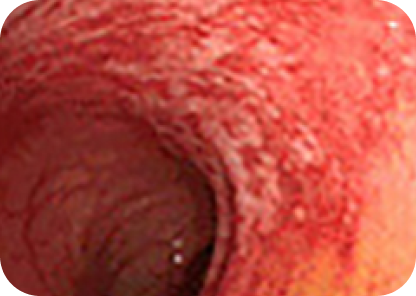

최근 대장항문 내시경의 해상도는 아래 사진과 같이 아주 뛰어난 상태로 1mm이하의 작은 병변도 확대해서 관찰이 가능합니다. 따라서 내시경 검사는 대장 용종과 대장암 뿐만 아니라 정상과 별 차이가 없어 보이는 미세한 조기 대장암도 진단할 수 있는 가장 정확한 검사법입니다.

아래 사진과 같이 5x5mm 크기의 작은 사각형을 실제 17인치 모니터에 꽉 차 보일만큼 정확하게 확대해서 관찰할 수 있으며 1mm 눈금보다도 작은 부분도 정확하게 관찰할 수 있을 정도로 정확합니다.